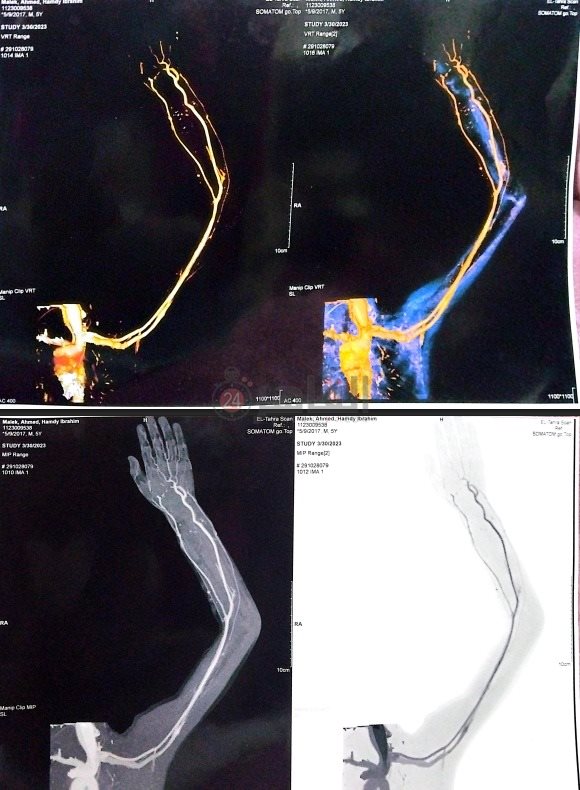

أطلقت والدة الطفل مالك، استغاثة عاجلة، مطالبة الجهات المعنية والجمعيات الخيرية بسرعة التدخل لإنقاذ نجلها، الذي يعاني من تشوه شرياني وريدي خطير، ويحتاج إلى جلسات حقن بالأشعة التداخلية داخل المركز الطبي العالمي، في ظل تدهور حالته الصحية واحتمالية تعرضه لفشل في عضلة القلب حال تأخر العلاج.

وقالت والدة الطفل مالك في تصريحات خاصة لـ القاهرة 24، إن حالة مالك ظلت لفترة طويلة دون تشخيص دقيق، موضحة أنه تم التوصل مؤخرًا للتشخيص الصحيح، وتحديد مكان العلاج المناسب لحالته.